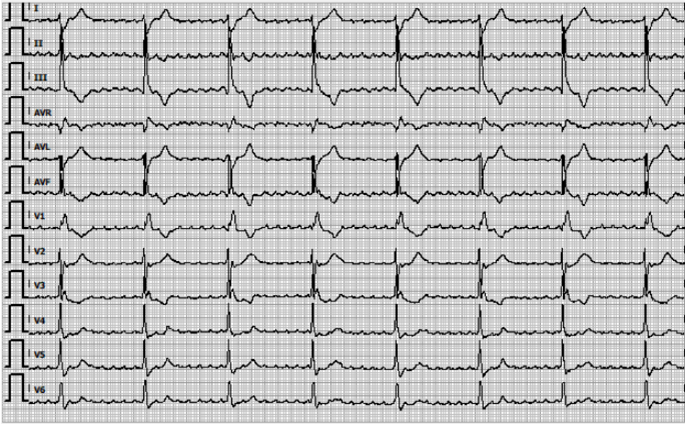

In April 2023, a 70-year-old male presented to the outpatient clinic of gastroenterology with complaints of dysphagia and weight loss. A diagnosis of iT3N1M0 adenocarcinoma of the distal esophagus was established. Prior to a planned curative esophagectomy, chemoradiotherapy was administered according to the regimen used in the CROSS-trial (1). In November 2023, following an R0 resection with residual pathological disease, the patient began adjuvant immunotherapy with nivolumab (2). Fourteen days after starting nivolumab, the patient developed complaints of palpitations and worsening dysphagia. Liver enzyme abnormalities were noted (ALAT 186 U/L, ASAT 263 U/L, LD 508 U/L) as well as thyroid dysfunction (TSH 0.001, FT4 51 pmol/L, FT3 17 pmol/L), with no signs of abnormalities in other endocrine axes. Hepatitis B/C/E serology and EBV/CMV IgM were negative, and abdominal ultrasound revealed no liver abnormalities. A suspicion of immune-related hepatitis, gastritis, and thyroiditis was raised. The patient was admitted to the hospital, and intravenous prednisone (80 mg) and propranolol (40 mg) were initiated. Two days later, liver enzymes showed insufficient improvement (Y-GT 83 U/L, ALAT 451 U/L, ASAT 196 U/L, LD 700 U/L), prompting the initiation of intravenous methylprednisolone (100 mg), which was increased to 200 mg after 2 days due to continued inadequate response. Six days later, the patient developed bradycardia (47 bpm) and required supplemental oxygen. An ECG revealed a complete AV-block with atrial flutter (Figure 1), along with elevated troponin (2729 ng/L) and CK levels (1090 U/L). Although MRI of the heart showed no significant abnormalities, immune-related myocarditis was considered. Mycophenolate mofetil (MMF) twice a day 1000 mg was started, and methylprednisolone was continued. Subsequently, the liver function improved. Due to persistent complete AV-block, a pacemaker was implanted.

Figure 1: ECG with an atrium flutter and total AV-block provoked by inflammation in myocarditis.